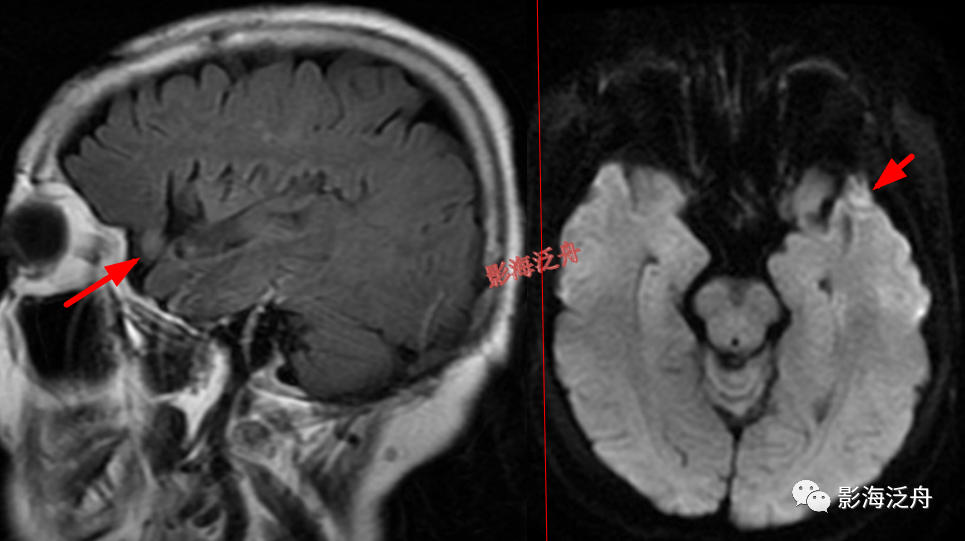

海绵窦、CPA区病变

左侧颈内动脉海绵窦段动脉瘤

伴血栓形成(红箭),绿箭为海绵窦段起始端,黄箭头所指为颈内动脉分段的重要解剖标志——前床突(颈内动脉分段可参考之前的文章 颈内动脉CTA分段(超实用))。

右侧CPA区(桥小脑角区)占位(红箭),呈T1WI及T2WI呈等低信号,邻近的听神经显示可(黄箭),因此倾向于诊断脑膜瘤。这个患者病史未诉听力障碍

,因此平时写报告千万不要等到患者有听力障碍才去观察两侧的听神经。

右侧CPA区听神经瘤

(红箭)。有些单位使用1.5T MR,对蝶鞍区及幕下结构的显示会不太理想,再加上本例患者的桥小脑角池发育的比较狭窄,不能把病灶很好的衬托出来,此时就很容易造成漏诊。